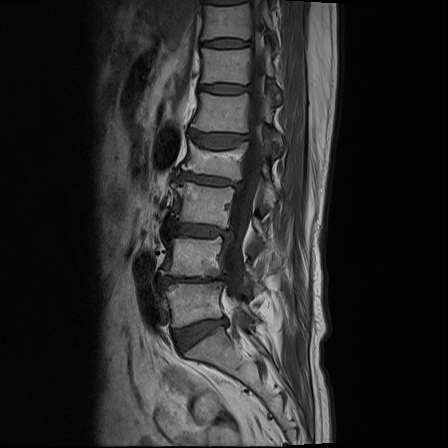

Ӵϲ ɿ ô ô 㸮 ٸ ̾ϴ. ϵ Ͻð ܻ 㸮 20⵿ ͽϴ. mri ˻ ɿ Ȳ ʹ ؼ Ȳ̶ ߽ϴ. ϻȰ ϰ 鼭 ½ϴ. ̴ ø鼭 Ͻô Ȳ ̷ ġ ص ȸ ϴ. δ Ҵµ, ù ȸԲ ˷ֽ ϰ β ϰ, ˷ֽ ü ƮĪ ϸ鼭 ȭǸ鼭 Ӵϲ ȸų ְ ǰ, β 鼭 ʴ β ؾϴ ŷο 1ϸ ijħ ڸ ǥ Ʈ ߽ϴ. ȸ ȭϽø鼭 Ϸ簡 ٸ ȸǽð 4ְ Ǿ Ǯ鼭 ¦ ҽϴ. ħ ȸ ȭϸ鼭 ڼ ü ƮĪ ϴ. ȥڼ Ͻʴϴ. ٳø鼭 ó Ͻ ʴϴ. ̾ ְ ̳ ߵ ʰ ϴ ȸԲ Ͻʴϴ. ʹ ϸ鼭 ϴ. Ȩ - ϱ ٴ Ȳ MRIԴϴ. |